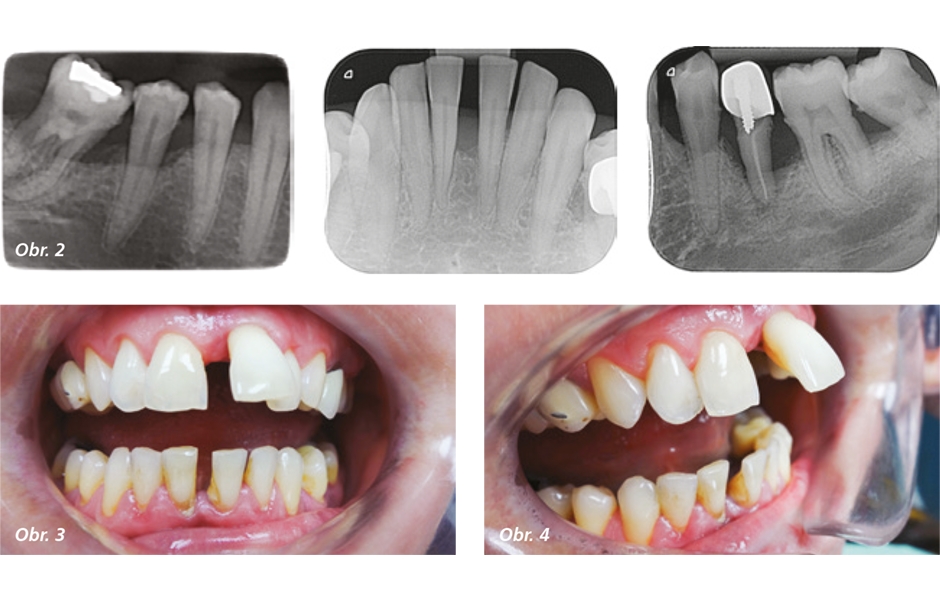

V prípravnej fáze sme vykonali komplexné vyšetrenie pacientky. Pacientka vyplnila anamnestický dotazník. Vykonali sme extraorálne vyšetrenie pacientky. Zistili sme asymetriu ľavej strany, čo bolo spôsobené postavením zuba číslo 21. Pokračovali sme v intraorálnom vyšetrení pacientky. Vyšetrili sme stav chrupu (RK4 d№35), stav hygieny (KOD – 75), stav mukogingiválnej oblasti (ťah frenulum labii superioris, šírka pripojenej gingivy pri d№31 a d№41 bola 0, prítomné gingiválne recesy), stav parodontu (CPITN 4-4-4/4-3-4, aktivita vačku s hnisavou exsudáciou d№21) a stav slizníc (bez patologického nálezu). Zhotovili sme aj rtg snímky – OPG a intraorálne snímky (obr.1, 2). Na základe tohto vyšetrenia sme pacientke stanovili diagnózu – kariologicky aktívna (RK4 d№35), parodontologicky aktívna – P3 agresívna parodontitída, generalizovaná forma (RP3 – RP4) (obr. 3, 4).

Obr. 2: Intraorálne rtg snímky, Máj 2015 / Obr. 3, 4: Fotodokumentácia, postavenie d№21 mimo zubný oblúk v maxile, Máj 2015